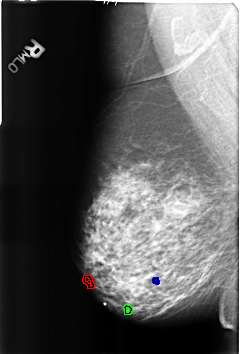

B_3178_1.RIGHT_MLO

FILE: B_3178_1.RIGHT_MLO.OVERLAY

TOTAL_ABNORMALITIES 3

ABNORMALITY 1

LESION_TYPE OTHER

ASSESSMENT 2

SUBTLETY 4

PATHOLOGY BENIGN_WITHOUT_CALLBACK

TOTAL_OUTLINES 1

BOUNDARY

ABNORMALITY 2

LESION_TYPE CALCIFICATION TYPE LUCENT_CENTER DISTRIBUTION N/A

ABNORMALITY 3